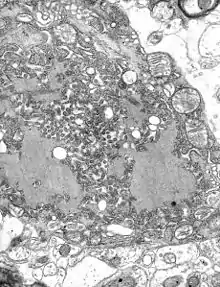

The rabies virus is the type species of the Lyssavirus genus, in the family Rhabdoviridae, order Mononegavirales. Lyssavirions have helical symmetry, with a length of about 180 nm and a cross-section of about 75 nm.[21] These virions are enveloped and have a single-stranded RNA genome with negative sense. The genetic information is packed as a ribonucleoprotein complex in which RNA is tightly bound by the viral nucleoprotein. The RNA genome of the virus encodes five genes whose order is highly conserved: nucleoprotein (N), phosphoprotein (P), matrix protein (M), glycoprotein (G), and the viral RNA polymerase (L).[22]

To enter cells, trimeric spikes on the exterior of the membrane of the virus interact with a specific cell receptor, the most likely one being the acetylcholine receptor. The cellular membrane pinches in a procession known as pinocytosis and allows entry of the virus into the cell by way of an endosome. The virus then uses the acidic environment, which is necessary, of that endosome and binds to its membrane simultaneously, releasing its five proteins and single strand RNA into the cytoplasm.[23]

Once within a muscle or nerve cell, the virus undergoes replication. The L protein then transcribes five mRNA strands and a positive strand of RNA all from the original negative strand RNA using free nucleotides in the cytoplasm. These five mRNA strands are then translated into their corresponding proteins (P, L, N, G and M proteins) at free ribosomes in the cytoplasm. Some proteins require post-translative modifications. For example, the G protein travels through the rough endoplasmic reticulum, where it undergoes further folding, and is then transported to the Golgi apparatus, where a sugar group is added to it (glycosylation).[23]

When there are enough viral proteins, the viral polymerase will begin to synthesize new negative strands of RNA from the template of the positive strand RNA. These negative strands will then form complexes with the N, P, L and M proteins and then travel to the inner membrane of the cell, where a G protein has embedded itself in the membrane. The G protein then coils around the N-P-L-M complex of proteins taking some of the host cell membrane with it, which will form the new outer envelope of the virus particle. The virus then buds from the cell.[23]

From the point of entry, the virus is neurotropic, traveling along the neural pathways into the central nervous system. The virus usually first infects muscle cells close to the site of infection, where they are able to replicate without being 'noticed' by the host's immune system. Once enough virus has been replicated, they begin to bind to acetylcholine receptors at the neuromuscular junction.[24] The virus then travels through the nerve cell axon via retrograde transport, as its P protein interacts with dynein, a protein present in the cytoplasm of nerve cells. Once the virus reaches the cell body it travels rapidly to the central nervous system (CNS), replicating in motor neurons and eventually reaching the brain.[5] After the brain is infected, the virus travels centrifugally to the peripheral and autonomic nervous systems, eventually migrating to the salivary glands, where it is ready to be transmitted to the next host.[25]: 317